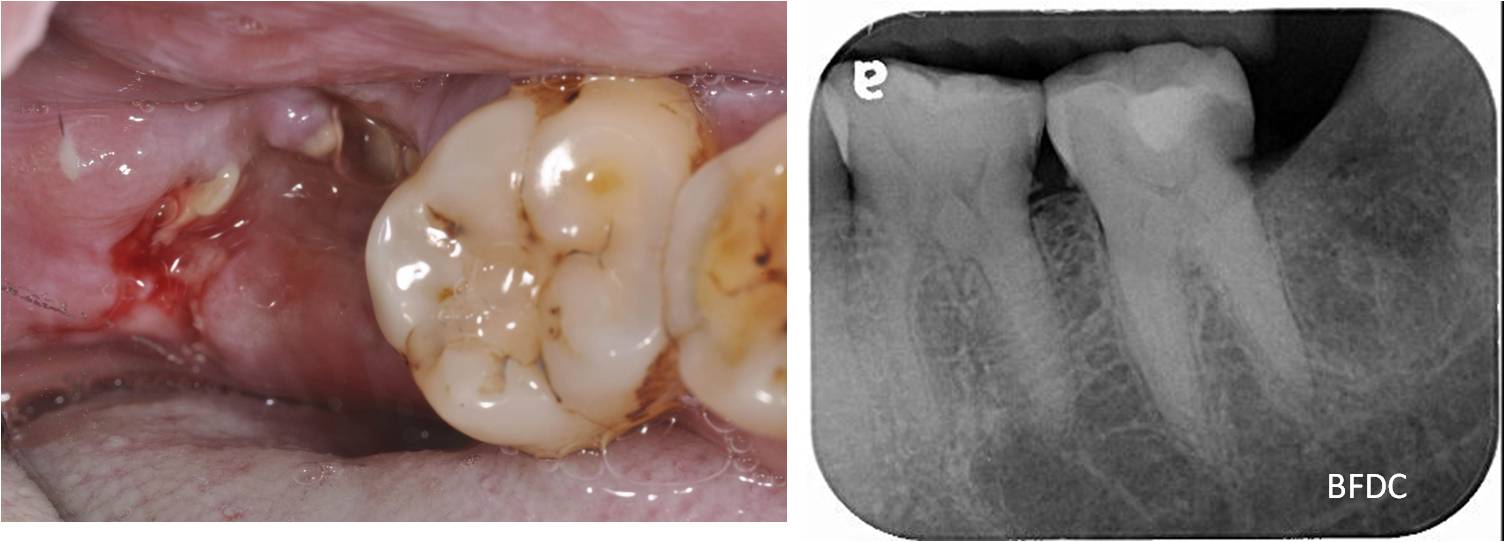

智齒已拔除,傷口逐漸復原

#37-顯微根管治療